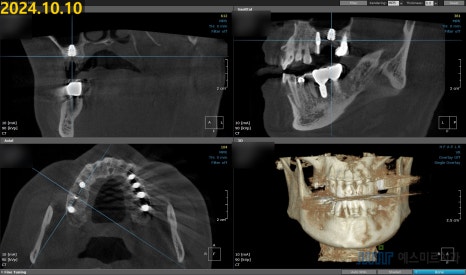

정밀 촬영과 검진 결과,

기존 임플란트 픽스처(뿌리)에 염증이 함께 발생한 상태였고

주변 골 손실도 상당해 제거 및 재수술이 필요한 상황이었습니다.

🦴 뼈이식 + 골유도 재생술 진행

픽스처 제거 후 주변에 남아 있는 염증 조직을 충분히 제거하고,

잃어버린 뼈를 보완하기 위해 뼈이식과 골유도 재생술을 함께 진행했습니다.

⚙️ 임플란트 재식립

Intrasurg 300 Plus 사용

뼈이식과 GBR이 완료된 부위에

카보(Kavo)의 Intrasurg 300 Plus 임플란트 전용 엔진을 사용해

새로운 임플란트를 즉시 재식립하였습니다.